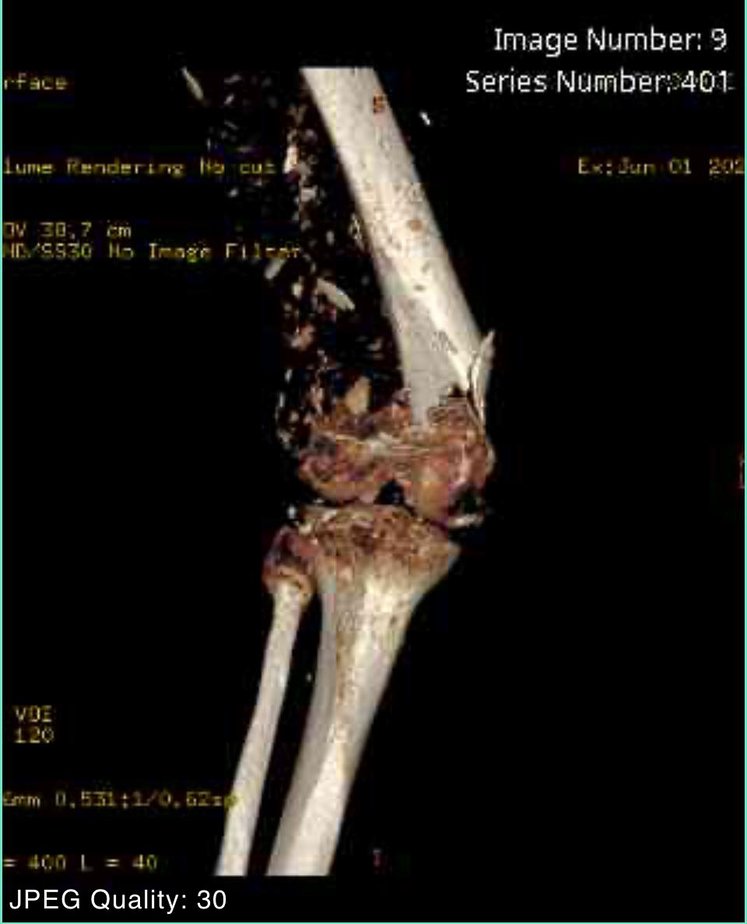

I am a 66 yr old C-7 SCI manual wheelchair user with 35+yrs post motorcycle accident. The last few years I have broken bones in both legs. The last injury happened in May 2024 when I fell transferring from wheelchair into my driver’s seat. I destroyed my left leg, breaking the femur, tibia and shattered my knee cap. Because of my lack of bone density the surgeon said he could not operate using screws or plates. He wanted to amputate above the knee. I had to teach him just because I don’t use my legs to walk I still use them to help in transfers. Explaining how I lift with my arms and then pivot on my legs during transfer made him decide on a Plan B. I would have to live with a non-union leg, meaning the femur is no longer connected to the knee. I immobilized the leg for 8 weeks then moved to a hinged brace permanently. Obviously it is not ideal, but is better than the alternative.